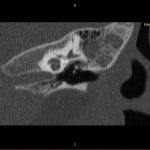

- Diagnosticul traumatismelor de bază de craniu

- Diagnosticul fracturilor:

- Complexe cranio-sinusale

- Complexe cranio-etmoidale

- Complexe cranio-orbitare

- Complexe cranio-faciale